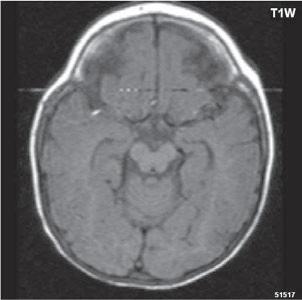

Zobrazení

D-W malformace je charakterizována hypoplazií vermis mozečku, rozšířením IV. mozkové komory, která se často cysticky vyklenuje dorzálně a může imitovat arachnoidální cystu, rozšířením zadní jámy lební a vysokým úponem tentoria s confluens sinum nad lambdovým švem. Okcipitální kost může být vlivem tlakových změn remodelována, existují i případy s porušením její kontinuity a encefalokélou. Hydrocefalus pozorujeme v 80 %, častá je přítomnost dysgeneze corpus callosum, schizencefalie.

D-W variant byl vyčleněn pro případy, kdy všechny základní příznaky nemusí být plně vyjádřeny nebo může některý zcela chybět. Bývá přítomna hypoplazie mozečku, což je dominantní příznak, IV. komora je obvykle rozšířena, někdy pozorujeme, že tvarem připomíná na axiální řezu „klíčovou dírku“, zadní jáma lební naopak rozšířena nebývá.

Obr. I.1.8a Dandy-Walkerova malformace, rozšířená IV komora (tvar klíčové dírky)

Obr. I.1.8b Dandy-Walkerova malformace, rozšířená IV komora široce komunikující s cisterna magna, hypotrofie mozečku (snímky zapůjčeny z archivu prim doc MUDr M Mechla, Ph D, MBA)

Obr. I.1.8c Dandy-Walkerova malformace, rozšířená IV komora široce komunikující s cisterna magna, hypotrofie mozečku (snímky zapůjčeny z archivu prim doc MUDr M Mechla, Ph D, MBA); stejný pacient jako na obr I 1 8b

Obr. I.1.8d Dandy-Walkerova malformace, rozšířená IV komora široce komunikující s cisterna magna, hypotrofie mozečku, vysoký úpon tentoria (šipka) (snímky zapůjčeny z archivu prim doc MUDr M Mechla, Ph D, MBA); stejný pacient jako na obr I 1 8b, c